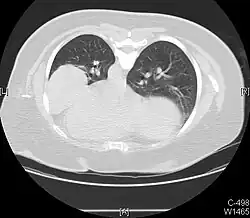

Tension pneumothorax

Tension pneumothorax is an emergent condition in which air gets trapped in the space between the chest wall and the lung. This space is referred to as the pleural space. Because air can't escape from this space, the air pocket grows larger and larger, resulting in the lung collapse closest to the pneumothorax. Forces are transmitted to the mediastinum and effectively "push" the mediastinal structures to the opposite side of the chest.[5]